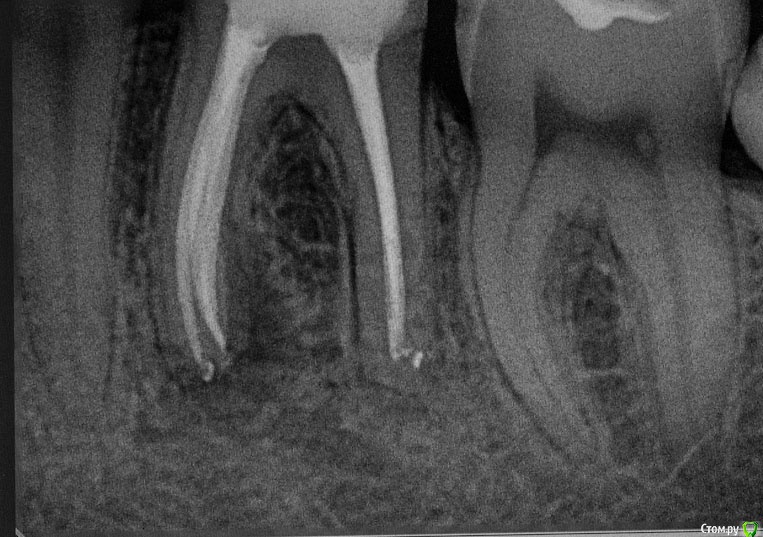

M@estro Опубликовано 27 января, 2016 Автор Поделиться Опубликовано 27 января, 2016 Повторное эндо ( ре-колл 7 месяцев) . 5 каналов в 3.6 . Обтурация - CWCT . Мех.обработка - Profile + m2 . Ca(OH)2 на 2 недели 12 Ссылка на комментарий